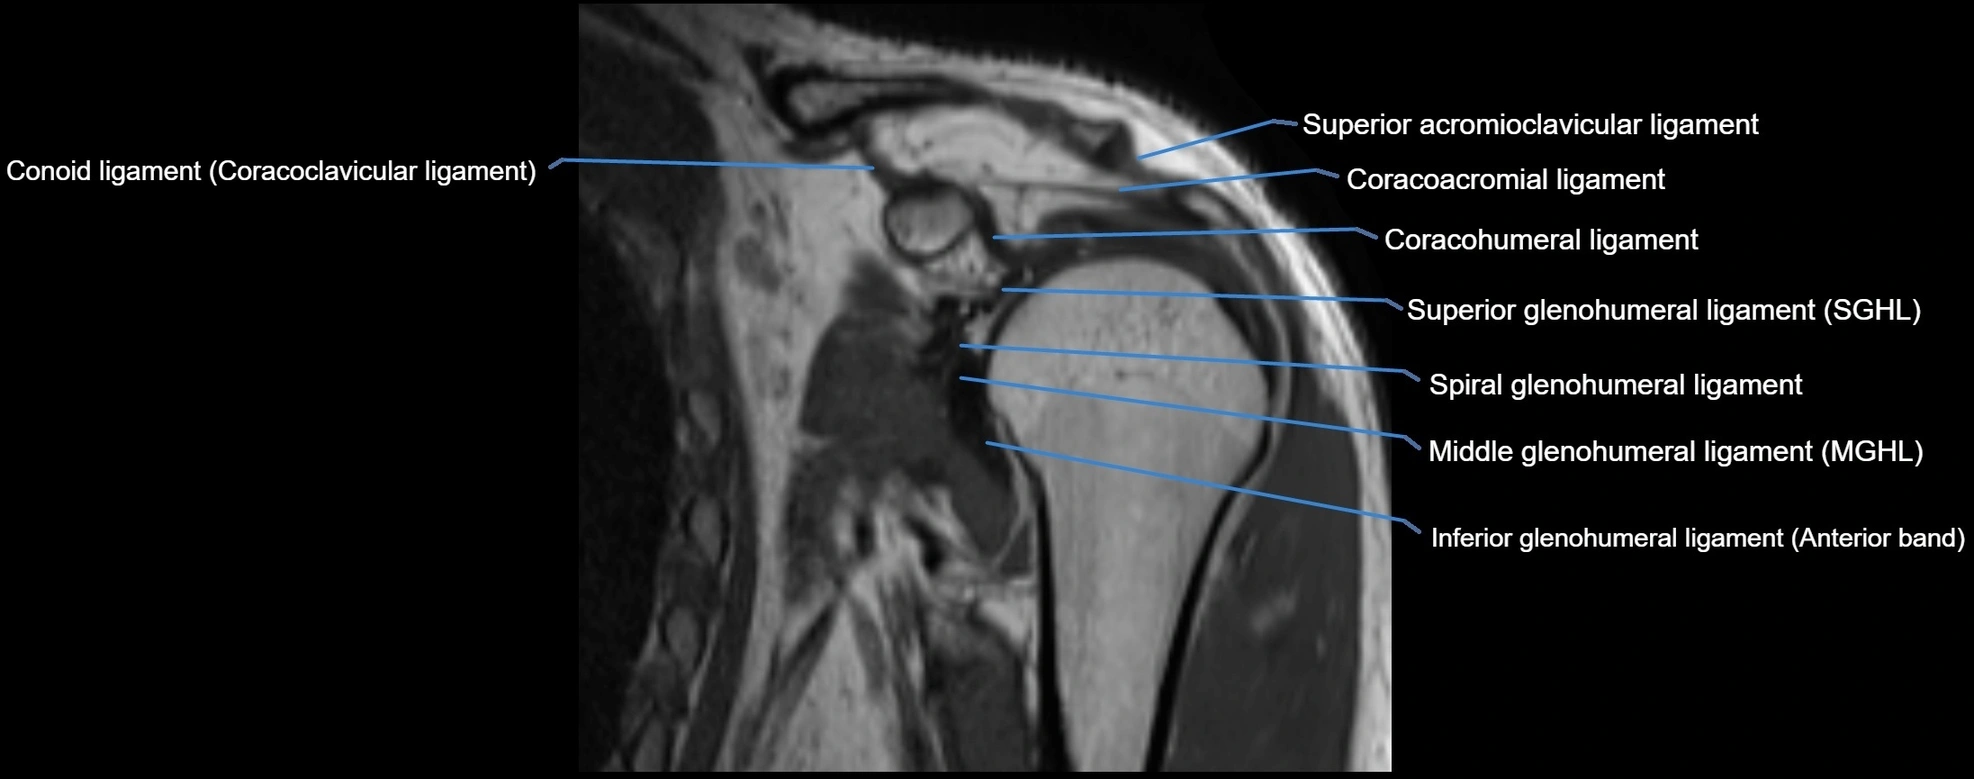

MRI Appearance

• T1-weighted images:

• Normal ligament: Low signal (dark linear band) spanning acromion to clavicle.

• Surrounding fat planes: Bright, delineating the ligament clearly.

• Marrow of clavicle and acromion: Bright due to fatty content.

• Tears: Discontinuity or irregular thickening with intermediate-to-bright signal.

• Chronic injury: Thinning, fraying, or irregular low-signal fibers with adjacent scarring.

• T2-weighted images:

• Normal ligament: Low signal, homogeneous.

• Partial tear or sprain: Focal hyperintensity or thickening.

• Complete tear: Discontinuity with fluid-bright gap between clavicle and acromion.

• Associated edema: Bright signal in distal clavicle or acromion marrow.

• STIR:

• Normal ligament: Dark linear band.

• Injury or inflammation: Bright hyperintense signal in and around ligament fibers.

• Highlights periligamentous soft-tissue edema, especially in acute trauma.

• Proton Density Fat-Saturated (PD FS):

• Normal ligament: Low signal, uniform thickness.

• Partial tear or sprain: Bright signal or contour irregularity.

• Complete tear: Clear discontinuity with bright signal gap and joint effusion.

• Excellent for assessing joint capsule, coracoclavicular ligaments, and periarticular edema.